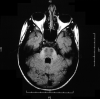

Autosomal recessive spastic ataxia of Charlevoix-Saguenay: a report of MR imaging in 5 patients

We present findings on MR imaging in 5 patients with autosomal recessive spastic ataxia of Charlevoix-Saguenay (ARSACS). In the literature, early atrophy of the superior vermis as well as progressive atrophy of the cerebellar hemispheres and cervical cord was described. We found linear hypointensity on T2 and T2 fluid-attenuated inversion recovery-weighted images in the pons in all of our 5 patients.